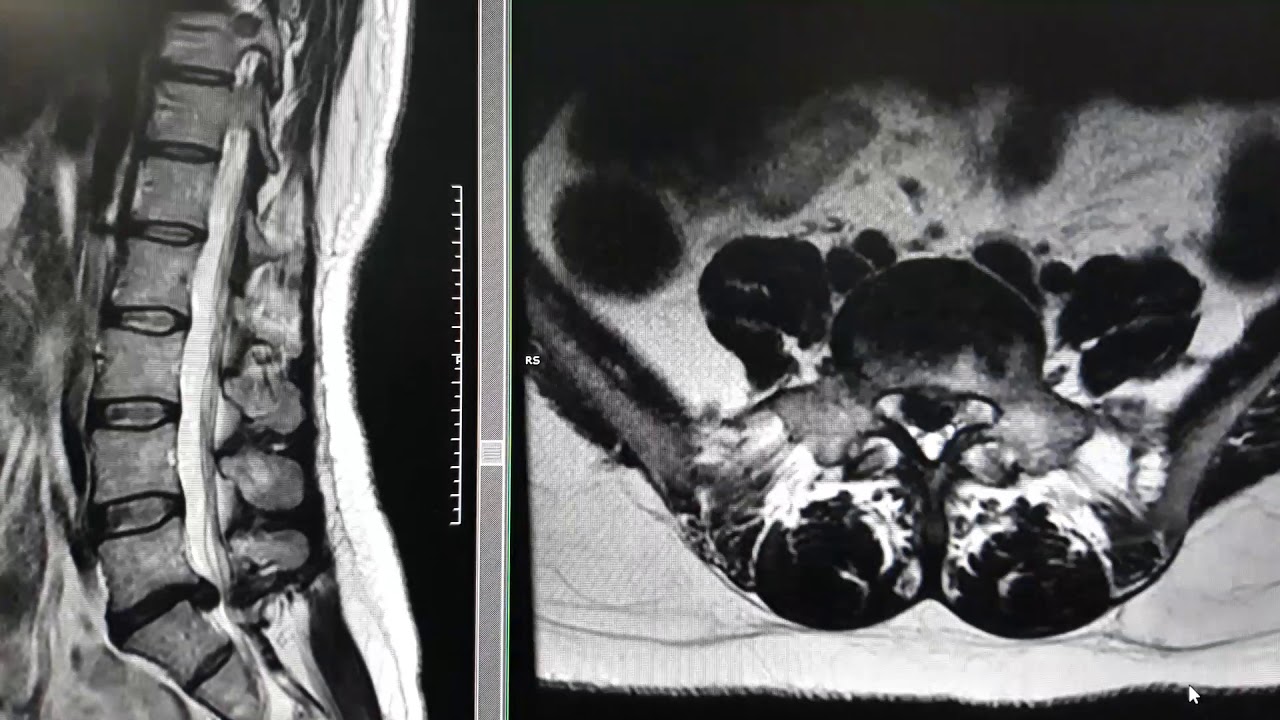

Identificar una hernia discal en una radiografía puede parecer complicado, pero no es tan aterrador como suena. Vamos a desglosarlo paso a paso. Primero, hablemos de cómo funcionan las radiografías. Las radiografías son imágenes que nos permiten ver la estructura ósea y, en algunos casos, los tejidos blandos. Aunque no son la herramienta definitiva para diagnosticar una hernia discal, pueden proporcionar pistas valiosas. En este artículo, exploraremos los diferentes tipos de radiografías, qué buscar en ellas y cómo interpretar esos signos que pueden indicar la presencia de una hernia discal.

¿Qué Buscar en una Radiografía para Identificar una Hernia Discal?

Ahora que sabemos qué tipos de radiografías se utilizan, es hora de aprender a identificar una hernia discal. Aquí hay algunos puntos clave a tener en cuenta.

Desplazamiento del Disco

El primer signo que buscamos es el desplazamiento del disco. En una radiografía, un disco herniado puede aparecer como una irregularidad en el espacio entre las vértebras. Si ves un disco que se ve más plano de un lado o que parece sobresalir, ¡ese podría ser el culpable!

Espacios Intervertebrales Reducidos

Los espacios intervertebrales son los lugares donde los discos se encuentran entre las vértebras. Si observas que estos espacios están más estrechos de lo normal, podría ser una señal de que el disco está degenerado o herniado. Es como si estuvieras viendo un globo que se ha desinflado; ya no ocupa el mismo espacio.